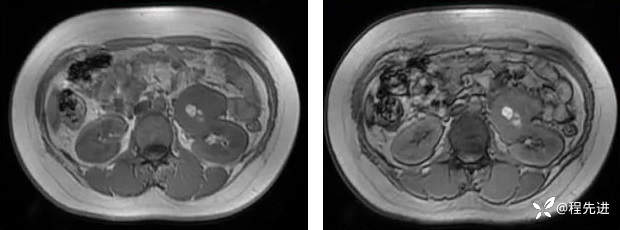

T1同反相位: